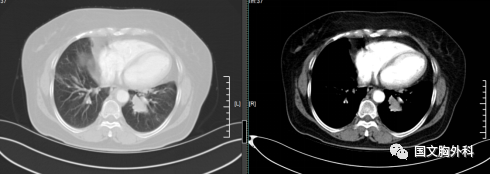

因病灶位置關(guān)系經(jīng)過支氣管鏡檢查未能明確病理,病灶包裹著血管CT穿刺風(fēng)險(xiǎn)巨大。